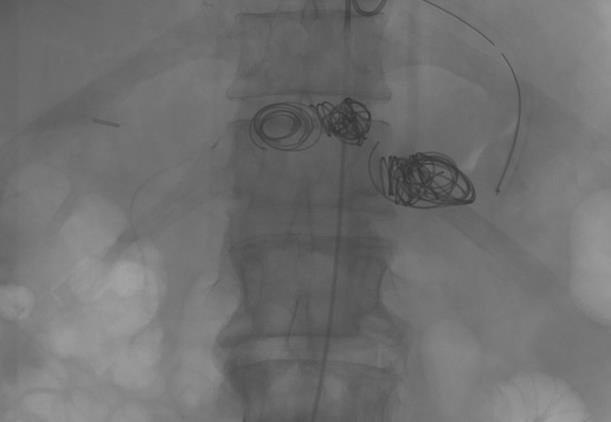

脾动脉瘤栓塞